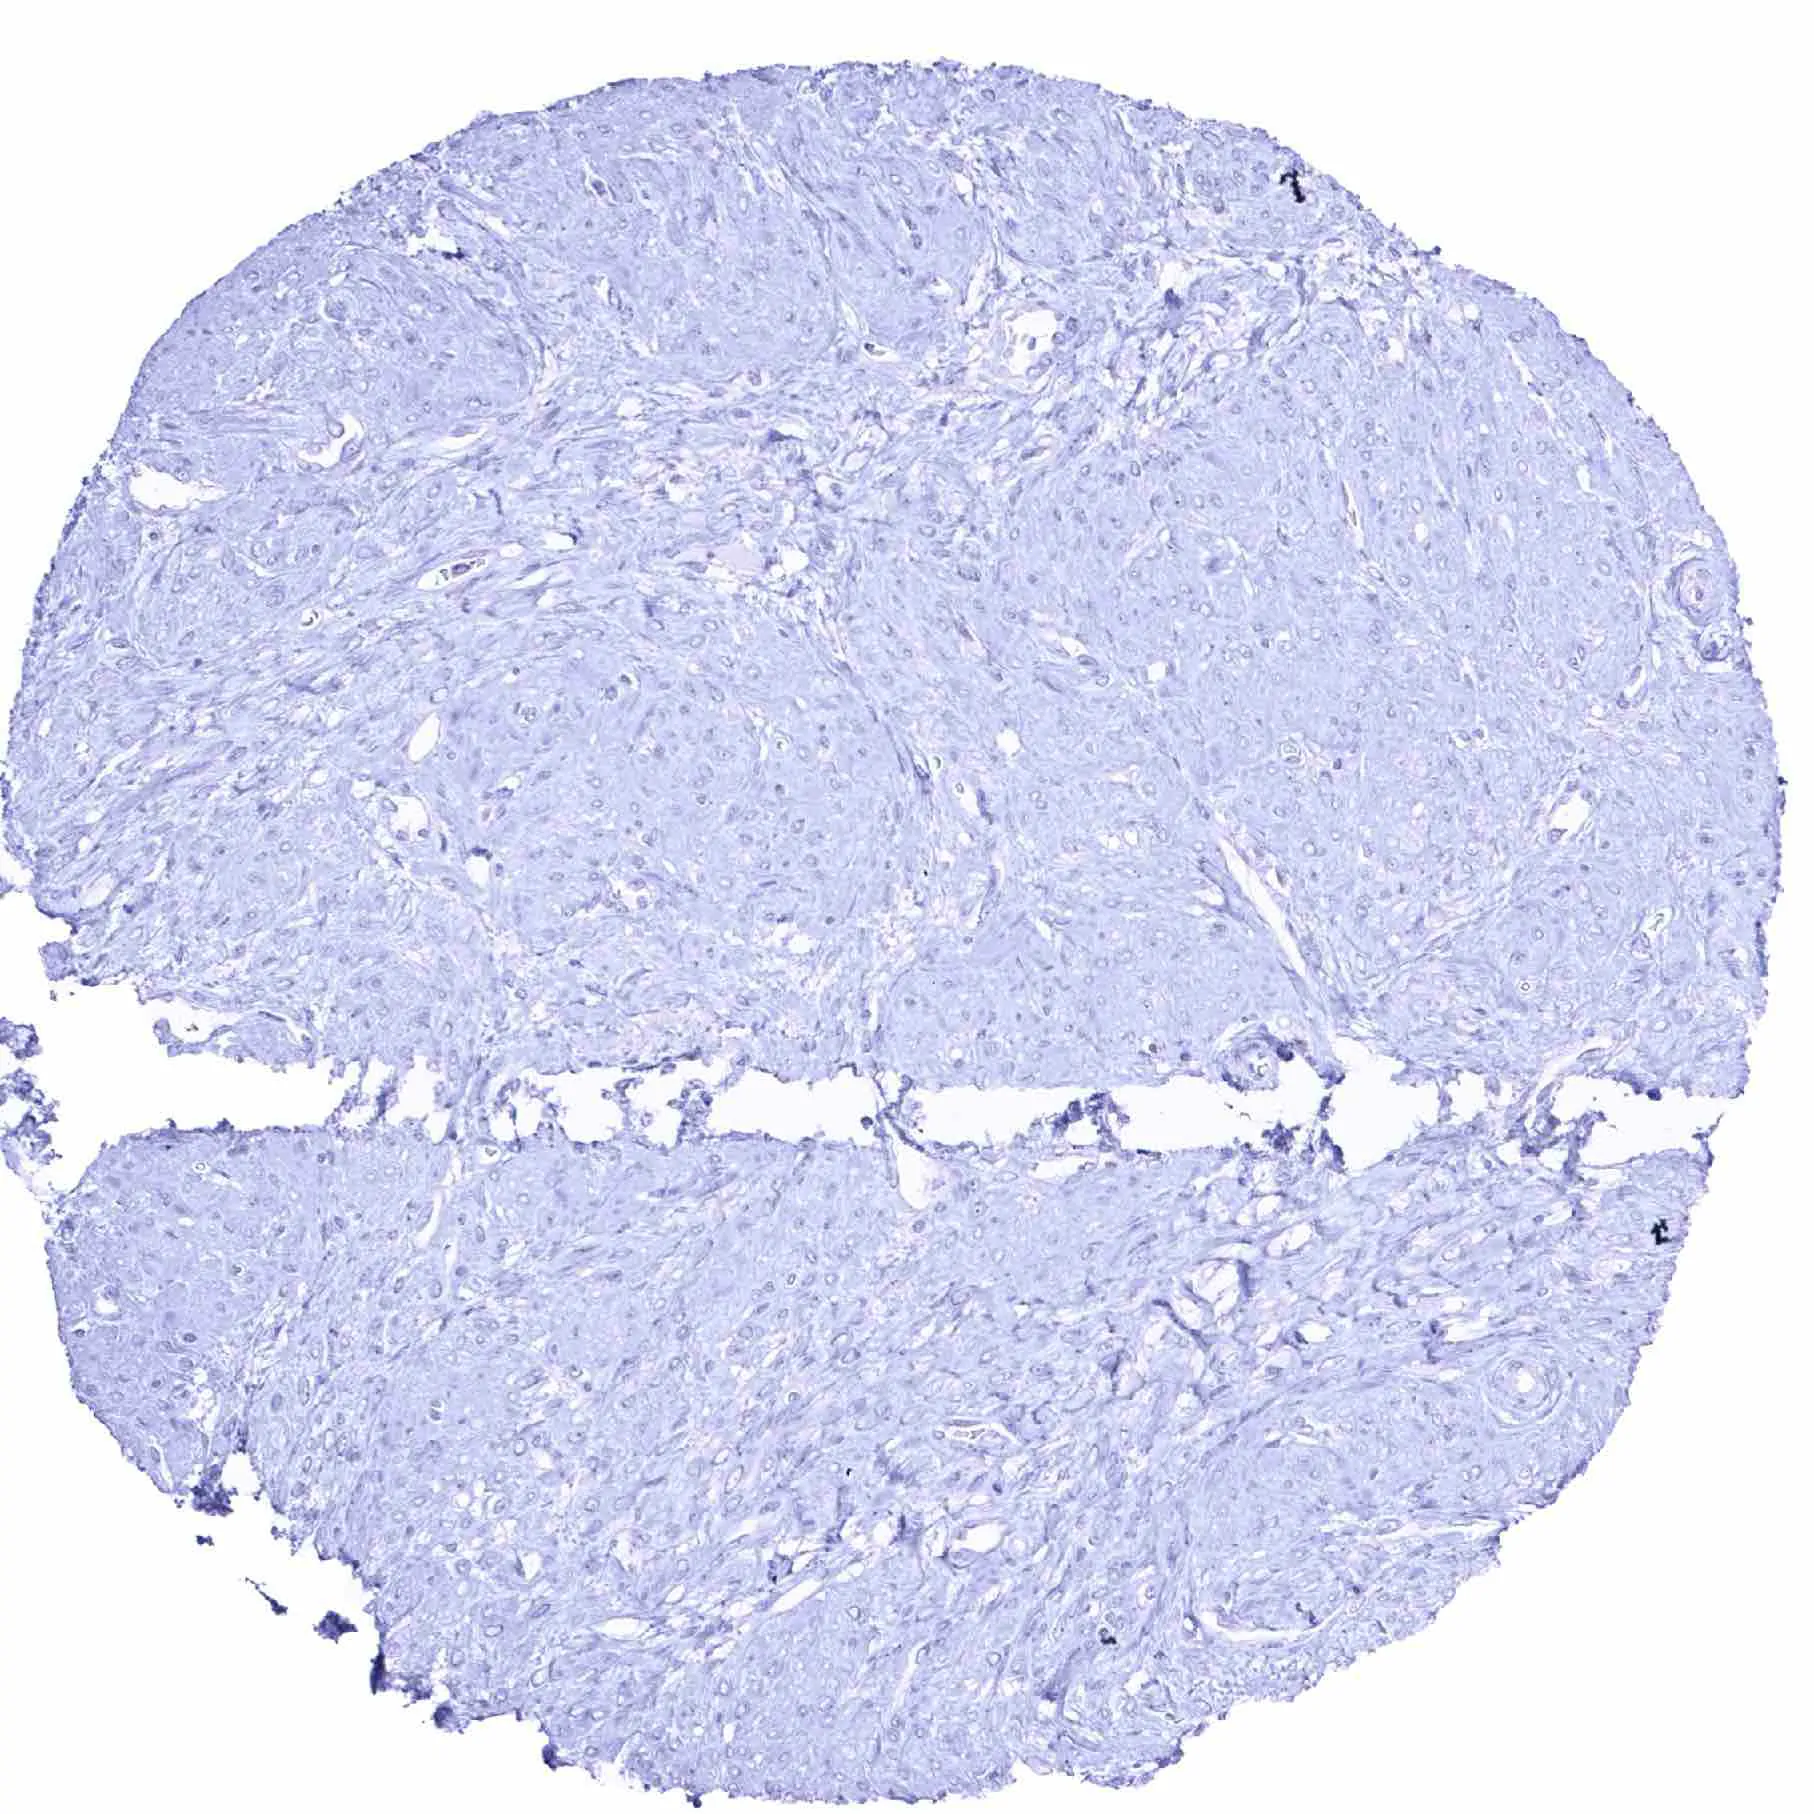

Aorta, media